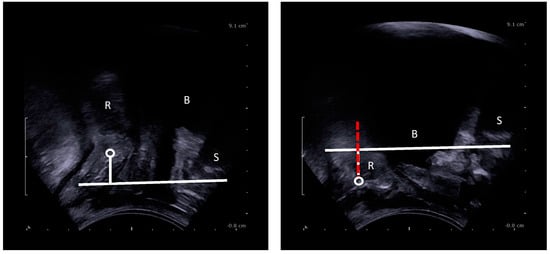

2.4. Imaging Analysis

Figure 3. Dynamic perineal descent on TPUS (red dashed): i.e., difference in movement of the ARJ between rest and maximum Valsalva. S = symphysis pubis, B = bladder, R = rectum, circle = ARJ.